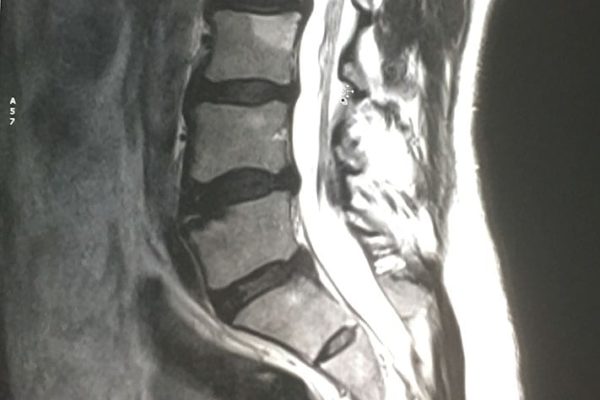

Il macchinario in dotazione presso il nostro Centro è una Risonanza Magnetica completamente aperta costituita da un magnete potente ma compatto a forma di G che fornisce un facile accesso al paziente ed un semplice posizionamento su un tavolo rotante, ampio, stabile e confortevole; si tratta infatti di un'evoluzione moderna della risonanza, nata per soddisfare le esigenze dei pazienti, in particolar modo di quelli che soffrono di claustrofobia e di tutte quelle persone che hanno difficoltà nel sottoporsi alla risonanza magnetica classica eseguita all'interno di una struttura cilindrica dallo spazio ridotto. Tali caratteristiche la rendono un’apparecchiatura ottimale nello studio dell'intera colonna vertebrale e delle articolazioni, permettendo un’ottima visualizzazione delle strutture ossee, cartilaginee, muscolari, tendinee e legamentose.